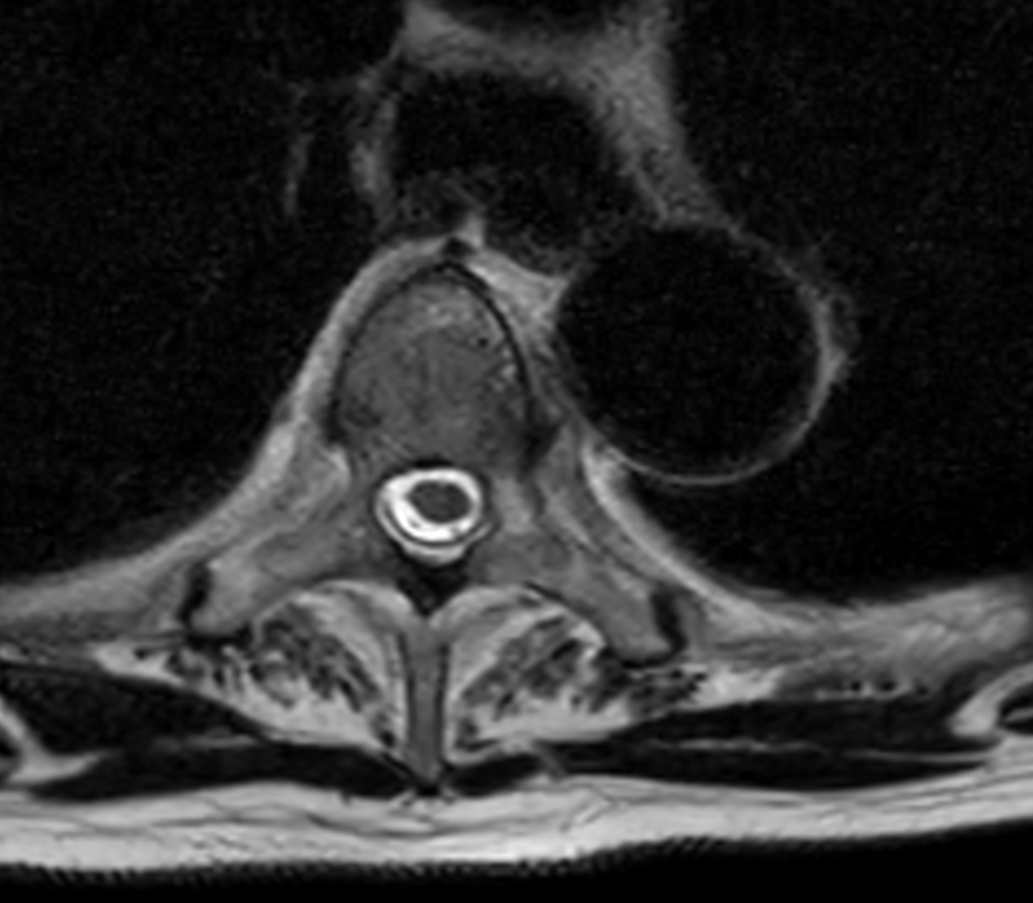

Axial T2w TSE - High res (T4)